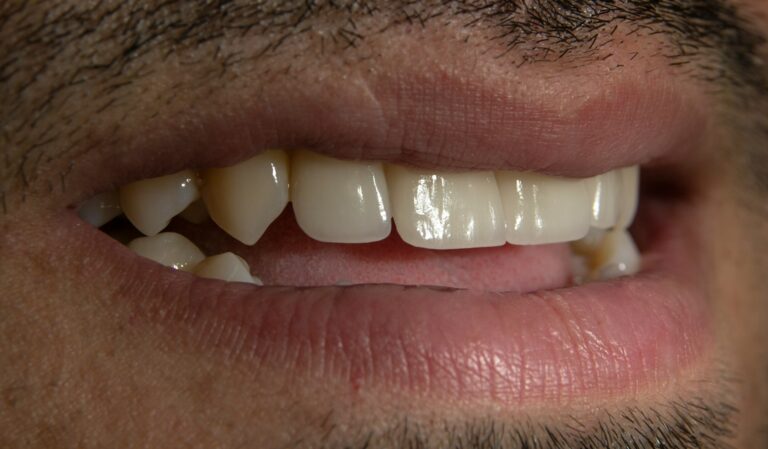

Czym jest elektrokoagulacja? Elektrokoagulacja to zabieg polegający na kontrolowanym wykorzystaniu prądu elektrycznego w celu zamknięcia naczyń krwionośnych oraz usunięcia zmienionych tkanek. W stomatologii metoda ta znajduje zastosowanie przede wszystkim w chirurgii i periodontologii. Stomatolog w nowoczesnej klinika stomatologiczna Kraków wykorzystuje…